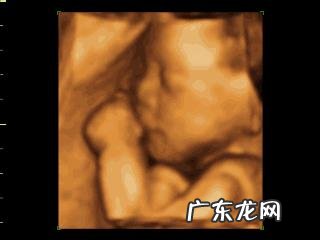

很高兴为您答疑解惑!怀孕后 , 四维彩超是孕期检查的最重要项目之一 , 主要是做胎儿“大排畸”检查 , 通过筛查 , 排除胎儿畸形的可能性 。该技术是目前为止较为先进的技术 , 对胎儿的发育状况 , 由里而外系统动画呈现 , 很直观 , 一目了然 。除了做排畸检查(如胎儿神经系统畸形 , 先心病 , 连体婴儿、唇腭裂等)外 , 还做一些常规检查(如胎儿的双顶径、头围、腹围、股骨长等 , 胎位和脐带状况、羊水状况等) 。

四维彩超最好选择大型正规医院(二级以上)去做 , 大医院的医生经验比较丰富 , 准确度高些 。由于做四维彩超的人比较多 , 所以需要提前预约 , 以免错过最佳时间 。一般 , 四维彩超预约需要提前15天~1个月左右时间 。方法一 , 你可以去医院直接预约 , 挂产科号 , 医生给你开单子 , 交完费后 , 去找彩超室的人 , 彩超室的人会帮你预约具体时间 。方法二 , 你也可以在网上预约 , 网上预约的前提是该医院开通了网上预约系统 。此外 , 如果你在某个医院建立了孕产保健手册 , 那么你肯定是定期去该医院做产检 , 产检期间 , 医生会根据你怀孕的孕周状况 , 以及该医院需要预约的时间周期 , 给你开单子 , 然后去超声检查室进行预约。四维超声检查的最佳时间是在22周~28周之间 , 最好在25周左右去做 , 因为此时胎儿结构已经基本形成 , 胎儿大小适中 , 羊水也较适中 , 胎宝宝在子宫内的活动空间较大 , 胎宝宝的骨骼回声影响较小 , 最重要的是此时做的图像也比较清晰 , 有利于胎儿畸形排查 。

通常孕22-28周都可以做四维检查 , 因为此时胎儿大小适中 , 羊水量充足 , 比较容易采集到清晰的图像 。

如果选择最佳时间的话 , 怀孕24-28周最好 , 因为孕24周左右是胎儿大脑发展高峰期 , 此时的胎儿结构已经形成 , 已经进入腹腔、大小合适、羊水量适中 , 在宫内的活动空间较大 , 胎儿骨骼回声影响比较小 , 图像也比较清晰(注意 , 如果是双胎或者多胎的话 , 需要更早一些 , 大约孕20周就可以检查了) 。